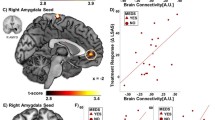

In the original report, the addition of the amygdala connectivity term led to a total 33% variance explained, a substantial increase of 21% over the variance explained by baseline social anxiety symptoms alone. In the replication dataset, the amygdala connectivity term explained an additional 2% of the variance (Fig. 1C; prediction R2 = 0.016, model-based R2 = 0.020). This improvement in prediction was marginally significant, model-based p = 0.097 and prediction R2 p = 0.101, rendering it unclear whether the small increase in predictive power afforded by amygdala connectivity was due to chance.

A The seed region for the connectivity-based predictive model: bilateral, anatomically defined amygdala (red). B Treatment response was predicted by a linear combination of greater amygdala connectivity with a subgenual cingulate/caudate/putamen cluster (yellow) and reduced amygdala connectivity with bilateral central sulcus clusters and right temporal-occipital clusters (blue). C Predicted treatment response for the compact model (including only baseline symptom severity, red points) vs. the full model (also including amygdala connectivity, blue points). Successful replication would be indicated by an improved prediction for the full model vs. the compact model. D Changes in prediction errors for the full vs. compact model for each subject. The inclusion of amygdala connectivity slightly improved model predictions (increase of 2% variance explained), with marginal statistical significance. Brain images were created using MRICroGL.

Visual inspection of the data confirmed that findings were not driven by outliers (Fig. 1D). We confirmed that all three terms in the model were approximately normally distributed, Anderson-Darling test, ps > 0.4.